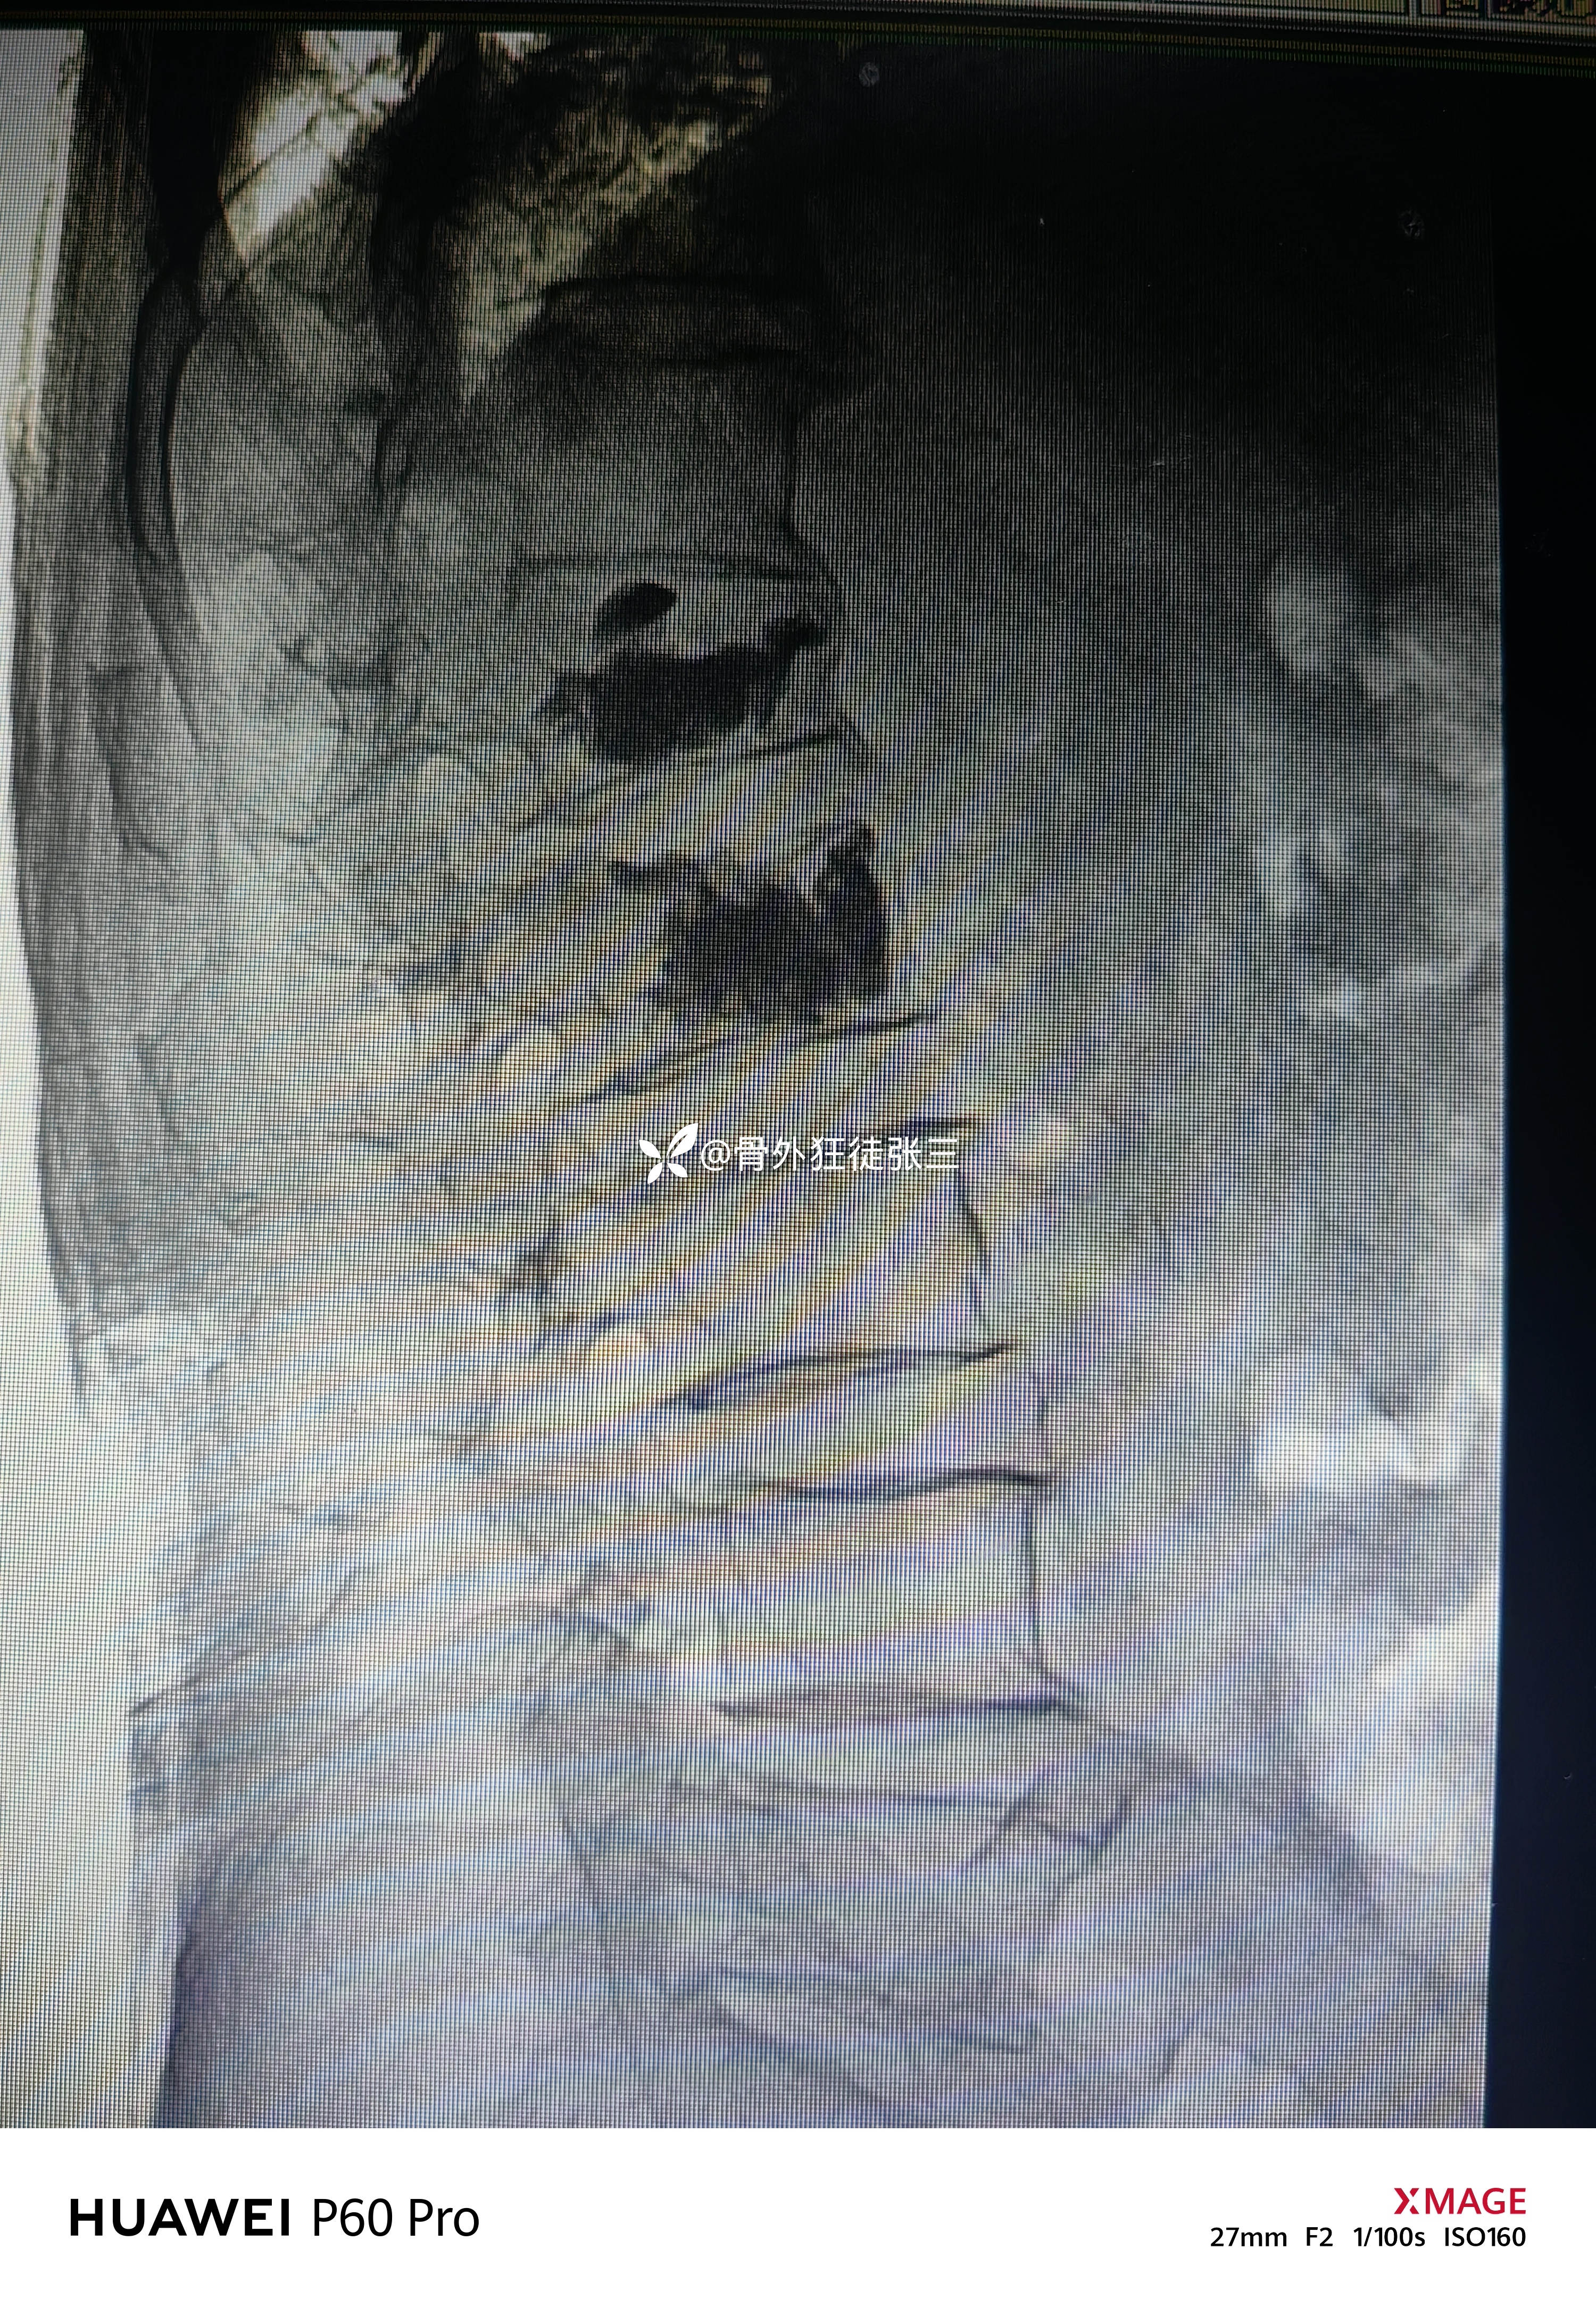

术后侧位

术前术后对比